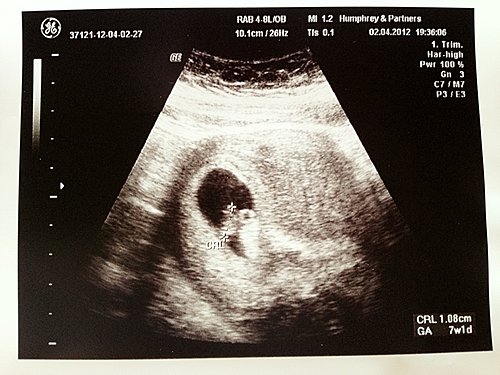

一照就見到胎囊入面有一 pat 白色嘢,靳醫生話呢 pat 白色嘢就係阿 b 啦,而家阿 b 的 size 有 1.08cm,電腦計出來有 7wks1d,預產期係 11月18日。

我問靳醫生有心跳未,佢話梗係有啦,仲指比我睇添,原來係一點白色閃閃下果個就係心跳了,之後我問靳醫生可唔可以比我聽下心跳聲,當然係無問題啦~

我再問靳醫生,阿 b 的心跳夠快未呀 ? 佢話照佢睇應該 1 分鐘 over 咗 120 下,正常無問題~

靳醫生再話其實心跳快慢其實無乜關係的,就算心跳一直好快,都唔代表阿 b 係健康,所以叫我哋唔駛咁介意快慢,同埋要 mon bb 的心跳,唔係就咁睇一陣就得,起碼要 mon 住半個鐘以上先可以分析到的~